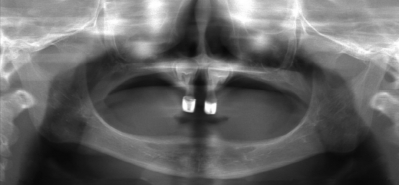

3歳の男児。食事が摂りにくいことを主訴として来院した。まず上顎両側乳前歯の形態修正を行った。その後義歯を装着することとした。初診時の顔貌写真と形態修正後のエックス線画像を別に示す。